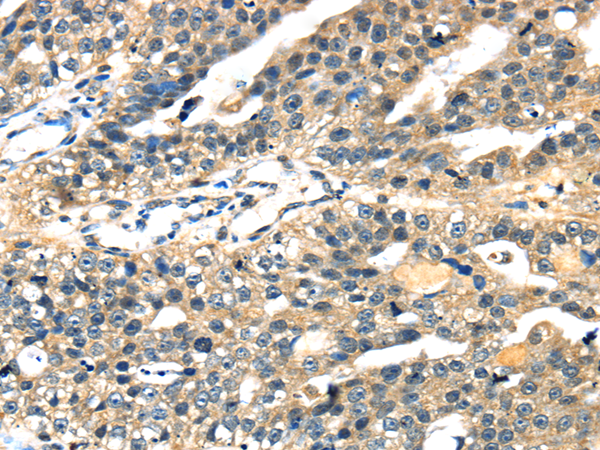

分类: 科研抗体货号: P08838别名: ABC7; ASAT; Atm1p; EST140535应用: IHC反应种属: Human, Mouse, Rat